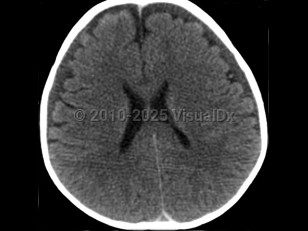

It is thought that the primary injury arises as a result of the multidirectional forces from shaking, leading to a form of whiplash injury associated with diffuse axonal injury, tearing of bridging veins, and subsequent intracranial bleeding. The secondary brain injury is due to a combination of hypoxia, ischemia, and brain edema. The end result is destruction of brain cells, a reduced supply of oxygen to brain cells, and brain swelling leading to varying degrees of neurological deterioration and occasionally death. Anatomically, the combination of a not-yet myelinated brain, a relatively heavy head upon weak neck muscles, and lack of control of the head and neck are factors that predispose babies to this form of injury.

Abusive head trauma may present with one or more of the following clinical features: subdural hemorrhage, retinal hemorrhage, and encephalopathy. Retinal hemorrhages are present in approximately 85% of cases and may be unilateral, but the diagnosis of abusive head trauma should not be excluded if they are absent.